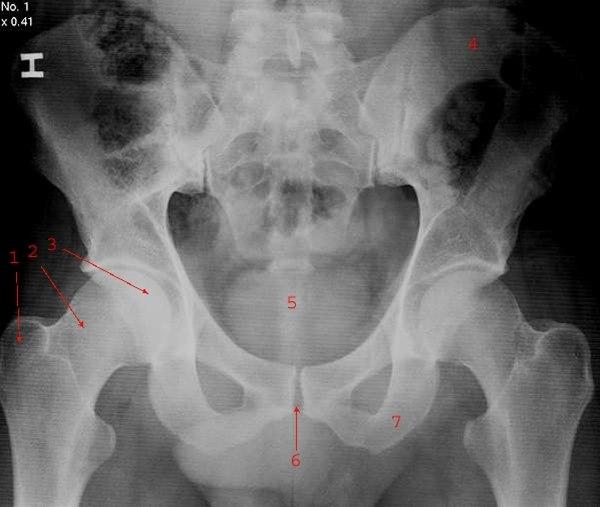

Normalt frontalbilde av bekken med sacrum og hofter

- Trochanter major

- Collum femoris(lårhals)

- Caput femoris (leddhode)

- Os ilium

- Os coccygis

- Symfysen

- Os ischii